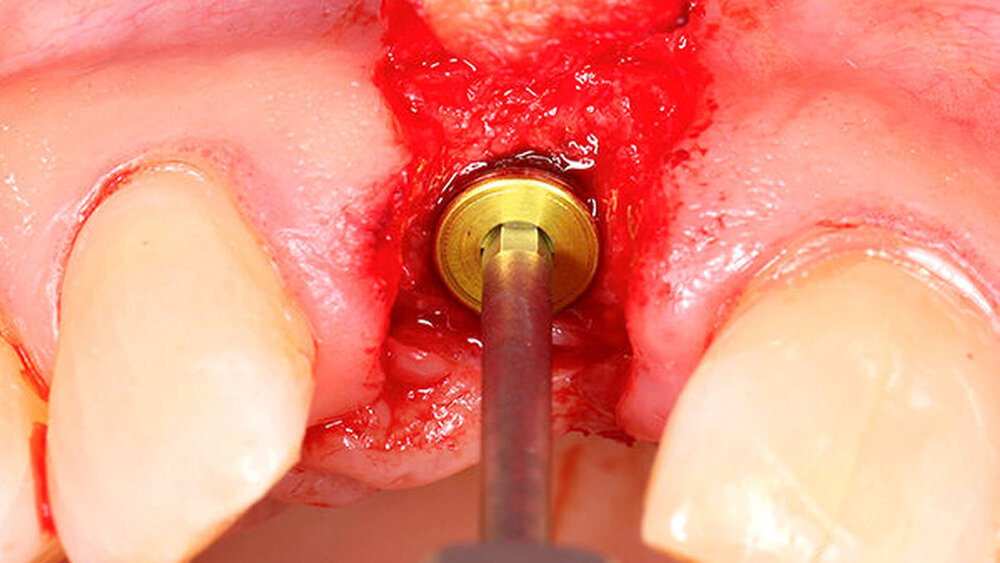

In welchen klinischen Anwendungen bietet das Implantat Vorteile?Hermann:Das neue CAMLOG PROGRESSIVE-LINE Implantat besticht durch sein innovatives parallel-konisches Makrodesign mit einem speziellen Gewinde, bei gleichzeitig bewährter Prothetikschnittstelle der Camlog-Linie. Dies bedeutet, dass in der chirurgischen Phase mit diesem Implantat eine zuverlässige Primärstabilität erzielt werden kann, speziell bei schwierigen anatomischen Voraussetzungen, wie z. B. bei der Sofortimplantation, bei reduzierter Kieferkammbreite oder konkav verlaufenden Alveoloarkämmen sowie bei weichem Knochen im Oberkiefer. Aufgrund des krestalen Verankerungsgewindes sehen wir zudem einen Vorteil bei der Platzierung des Implantats im Zusammenhang mit einer simultanen, offenen Sinusbodenelevation bei stark reduzierter Restknochenhöhe (2–3 mm). Auch einzeitige Verfahren lassen sich einfacher durchführen. Denn auch im kompromittierten Knochen erreicht das Implantat eine hohe vorhersagbare Primärstabilität.

Sind dann auch eher Sofortversorgungsprotkolle umzusetzen?Hermann:Die erzielte Primärstabilität ist in den meisten Fällen so hoch, dass eine sofortige provisorische Versorgung/Belastung möglich ist. Somit können wir unseren Patienten effiziente Behandlungsabläufe anbieten. Die Effizienz zeigt sich beispielsweise auch bei der Reduktion der Bohrschritte durch ein flexibles Bohrprotokoll. Gerade im weichen Knochen benötigen wir meist nur drei Bohrschritte bis zur Insertion des Implantats und erzielten eine exzellente Primärstabilität durch eine geringere Aufbereitung des Implantatbetts. Auf den zusätzlichen Einsatz nicht-ablativer Techniken (Osteotome) kann häufig verzichtet werden. Ein Teil der 80 von uns gesetzten PROGRES ‧ SIVE- ‧ LINE Implantate befindet sich bereits in der prothetischen Nachkontrolle. Das klinische und prothetische Outcome ist hervorragend. Es gibt weder chirurgische Komplikationen noch Probleme bei der Einheilung, und die prothetische Versorgung funktioniert perfekt.